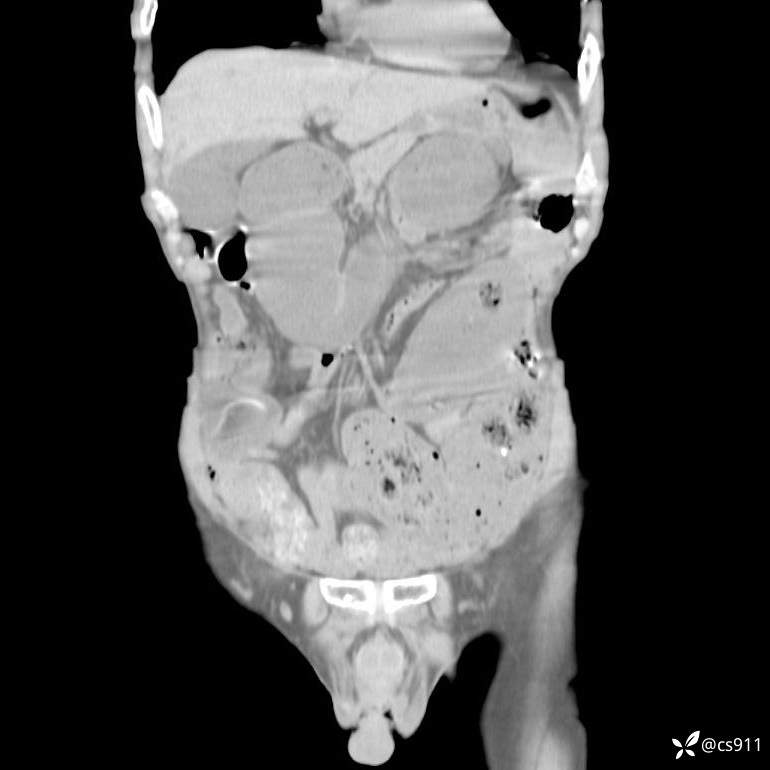

急腹症之急诊CT,原因?答案公布

男,77岁,腹痛、腹胀伴恶心呕吐1天。呕吐胃内容物,非喷射性呕吐,有咖啡色样胃内容物,诉有胃穿孔病史。查体:全腹平,下腹部压痛,全腹无反跳痛,叩诊呈浊音,移动性浊音阴性,肠鸣音减弱,1-2次/分。肛检:直肠未扪及明显肿物,可触及大量粪块。

T 36.6℃ P 80次/分 R 26次/分 BP 100/60mmHg

白细胞(WBC) H 14.55 10e9/L 4-10

中性粒细胞百分率(NEUT%) H 85.7 % 40-75

血淀粉酶(AMY) HH 1859 U/L 35-135

癌胚抗原(CEA) H 27.44 ng/ml 0-5

呕吐物 潜血试验 * 阳性 阴性

患者轮椅入室检查神志清楚, 能配合摆位和呼吸